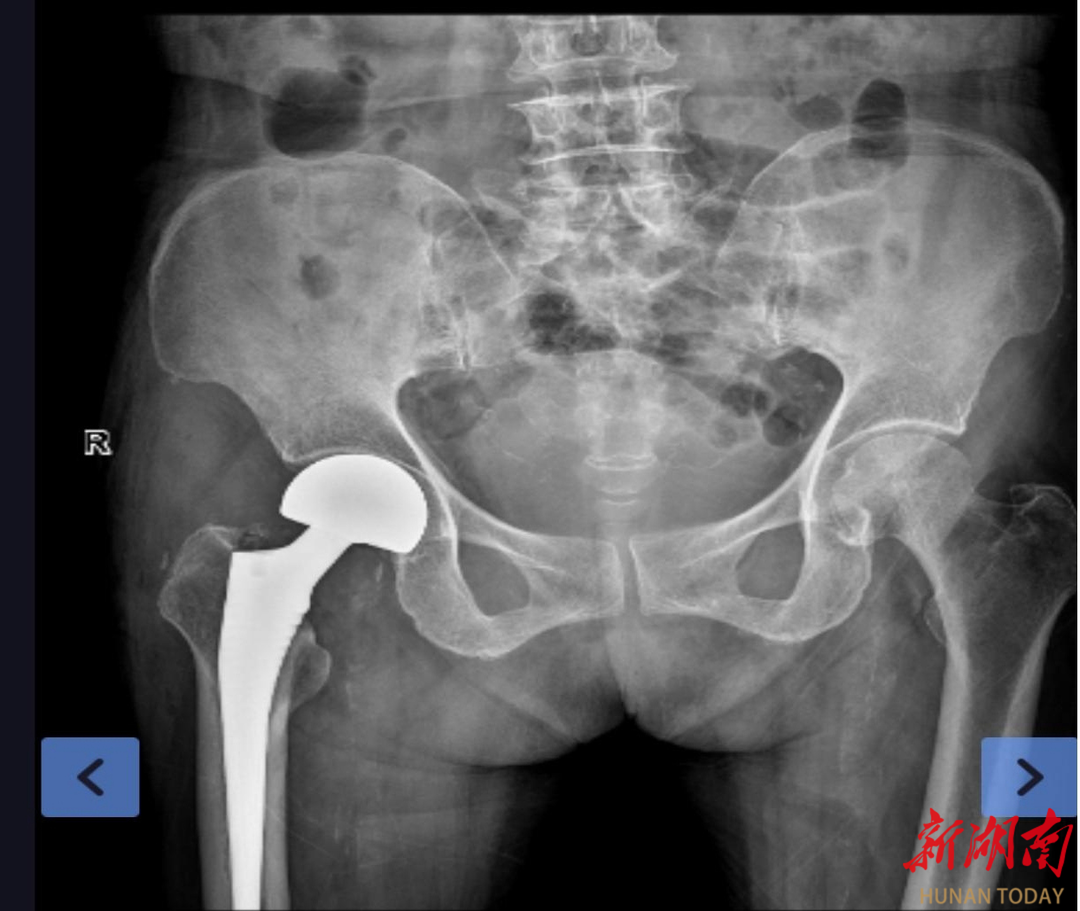

(术后X片检查)

9月30日,麻醉科采用“神经阻滞+全麻”的优化方案,为手术筑起了坚实的安全屏障。袁枭带领副主任医师唐海斌、医师李直刚顺利为患者实施手术